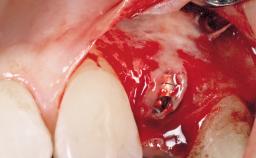

Surgical treatment of a 68-year-old female patient with a distal extension situation in the left mandible. As the CBCT analysis reveals, the bone crest anatomy in the area is not ideal and necessitates an augmentation procedure to achieve a good long-term prognosis for the planned implants and their prostheses.

After the placement of three diameter-reduced two-piece implants the bone is augmented with autologous bone chips and DBBM particles to enlarge the crest volume. The surgery is completed with the application of two membrane layers and primary wound closure.